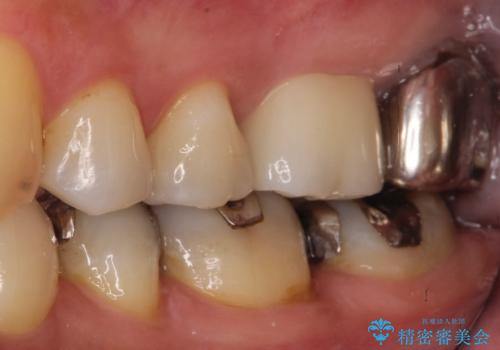

【根管治療】未処置根管を有した歯の再根管治療

- 定期検診にて虫歯を見つけたため、根管治療からオールセラミッククラウンによる修復治療を行いました。

上顎第一大臼歯の近心根にはほとんどの場合、神経の管が二本あることが多いです。顕微鏡を用いることで見逃すことなく治療が行えました。